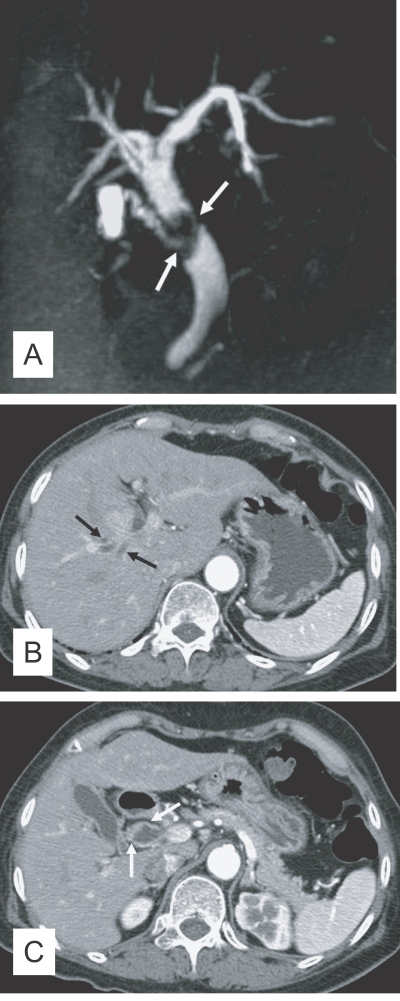

Fig. 3

Contrast-enhanced CT findings of the liver in clonorchiasis patients. A. A 52-year-old man, who underwent liver transplantation in China 1 month before CT examination, shows diffuse and mild dilatation of the peripheral intrahepatic bile ducts (arrows). The transplanted liver had been infected with C. sinensis. B. Periductal enhancement (arrows) with the thickened bile duct walls on hepatic arterial phase of dynamic study, which possibly represents active infection, in a 61-year-old man.

Fig. 3 Contrast-enhanced CT findings of the liver in clonorchiasis patients. A. A 52-year-old man, who underwent liver transplantation in China 1 month before CT examination, shows diffuse and mild dilatation of the peripheral intrahepatic bile ducts (arrows). The transplanted liver had been infected with C. sinensis. B. Periductal enhancement (arrows) with the thickened bile duct walls on hepatic arterial phase of dynamic study, which possibly represents active infection, in a 61-year-old man.

The CT finding of clonorchiasis is diffuse dilatation of the peripheral intrahepatic bile ducts, without dilation of the larger bile ducts or extrahepatic ducts (Fig. 3A). This finding is known to be the pathognomonic findings of clonorchiasis (Lim, 1990), however, it is also observed in cured infection.

In contrast to sonography showing an increased echogenicity of the ductal wall, CT failed to show thickening of the bile duct wall (Choi et al., 1989). A recent experimental study, however, suggested that an active infection could be differentiated from cured clonorchiasis by using the periductal enhancement with the thickened bile duct walls on dynamic contrast-enhanced CT (Lee et al., 2003). The contrast-enhanced CT visualized a characteristic finding, transient hepatic attenuation differences (THAD). The finding was interpreted as an outcome of new vascularization in the thickened bile duct wall, which disappeared after cure of clonorchiasis (Fig. 3B). They also asserted that some adult worms were demonstrated on their thin-section CT scans (Lee et al., 2003).